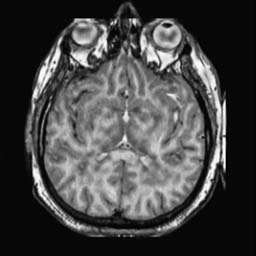

To demonstrate the effectiveness and efficiency of the proposed image fusion method , we conduct a set of comparative experiments on three image datasets. The first is composed by 8 pairs of multi-modal medical images and the second one contains 15 pairs of multi-focus gray or color natural images. These two datasets are often used in many related papers and some examples are shown in Figure 3(a) and Figure 3(b). The third one is a new multi-focus cervical cell image dataset collected by ourselves, which consists of 15 groups of color images and each group contains a series of multi-focus cervix cell images with size of or , etc. Some source examples are shown in Figure 3(c). Our source code implemented in C++ along with the new multi-focus cervical cell image dataset is available online.

We first evaluate the performance of the proposed method under varying total number of octaves and number of layers sampled per octave. The fused images of a pair of multi-modal medical images with different and are shown in Figure 4. In this example, on the one hand, when only 1 or 2 octaves are involved in constructing the DoG pyramid, the fused images fail to keep the integrity information of large size objects (e.g. eyeballs), while by increasing the value of , the integrity information of eyeballs is preserved. On the other hand, although not as significant as the increase of octave numbers , the fused image can contain more details by the increase of layer numbers . The corresponding objective quality metrics are shown in Figure 5. As shown in Figure 5(a), most of the metric values are improved as the number of octaves increases with the fixed layer numbers 3 in the global tendency and each of them tends to be stable when the number of octaves is 5. To get a relatively good quality from Figure 5(b), we can notice that some of the metric values can get a good performance when the number of layers is 3, such as the MI, SSIM, QI and VIF, though there are only a little change of all the metric values by increasing the number of layers with the fixed octave numbers 5. Because it will result in more computation burden with the increase of the value and , and for different kinds of source images, there are different performance with the diverse parameter settings. To get a trade-off between them in our experiments, we set for the multi-modal dataset, for the natural datasets and for the multi-focus cell dataset, respectively.

Figure 6 shows the fused images obtained by different methods with the multi-modal source images shown in Figure 3(a). As shown in these figures, the proposed method can produce images which preserve the complementary information of different source images well. Moreover, due to the scale-invariant structure saliency selection, our method can keep the integrity information of large size objects and the visual details simultaneously. Although the fused image generated by other methods can also capture the details to some extent, all of them fail to keep the integrity information of large size objects such as the eyeballs. Furthermore, from Figure 6(k)-6(t), the DTCWT, GFF, IM and NSCT methods may decrease the brightness and contrast while the proposed method can preserve these features and details without producing visible artifacts and brightness distortions.